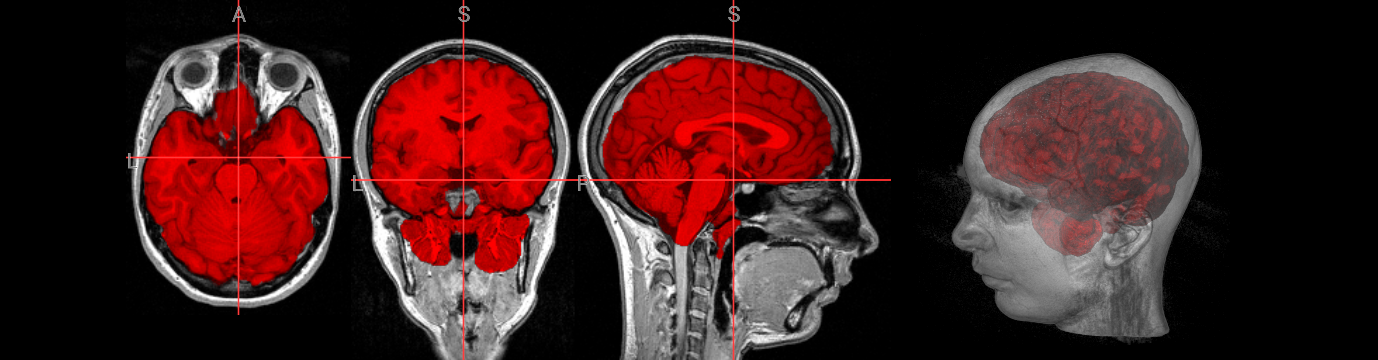

Dealing with large FOV images#

Problem: Large amount of neck/extra tissue confuses brain detection (initial brain surface is initialised too low):

! bet ./fsl_course_data/intro/bighead.nii.gz ./output/bighead_brain

nv.load_volumes( [{"path": "./fsl_course_data/intro/bighead.nii.gz", "colormap": "gray"},

{"path": "./output/bighead_brain.nii.gz", "colormap": "red"}])

Image(url='https://raw.githubusercontent.com/NeuroDesk/example-notebooks/refs/heads/main/books/images/fsl_course_bet_bighead.png')

Solutions:

Crop the image first to remove the neck:

robustfov -i input -r output_crop(recommended)Leave large FOV, but set brain centre-of-gravity:

-c <x y z> option(manual coordinate specification)Robust brain centre estimation:

-R option(iterates BET several times)

Different images may need different approaches - having multiple strategies available is essential for handling problematic cases.

Recommended Practice: Combine cropping with -R option for most robust results across different image types:

nv.load_volumes( [{"path": "./fsl_course_data/intro/bighead.nii.gz", "colormap": "gray", "opacity": 1.0},

{"path": "./output/bighead_crop.nii.gz", "colormap": "blue", "opacity": 1.0}])

Image(url='https://raw.githubusercontent.com/NeuroDesk/example-notebooks/refs/heads/main/books/images/fsl_course_bet_bighead_crop.png')

nv.load_volumes( [{"path": "./output/bighead_brain.nii.gz", "colormap": "gray"},

{"path": "./output/bighead_crop_brain.nii.gz", "colormap": "red"}])

Image(url='https://raw.githubusercontent.com/NeuroDesk/example-notebooks/refs/heads/main/books/images/fsl_course_bet_bighead_crop_brain.png')